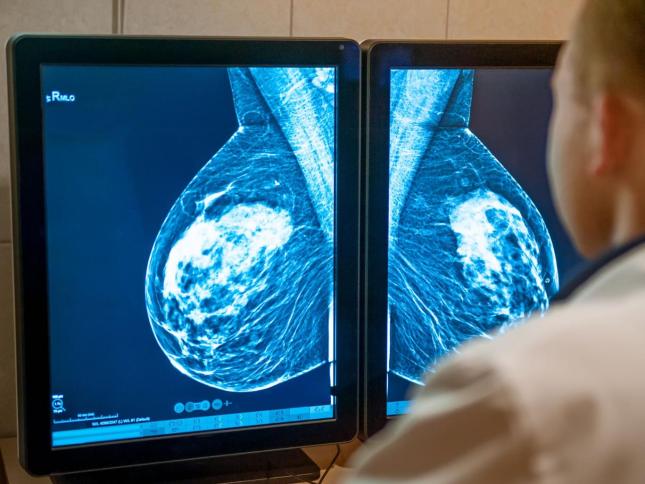

در ایران، اغلب سرطان پستان در مرحله دو تشخیص داده میشود